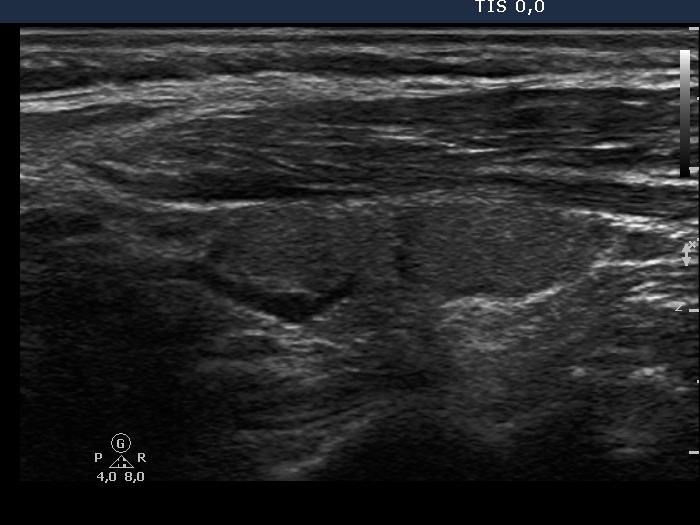

The operated thyroid - case 49 (ultrasonographic picture 5)

Left lobe, longitudinal scan. The lobe seems to be consisted of two or three parts. However, the echogenicity of these areas is identical, and only the deeply hypoechoic vascular and the moderately hypoechoic fibrous structures make the appearance nodular.